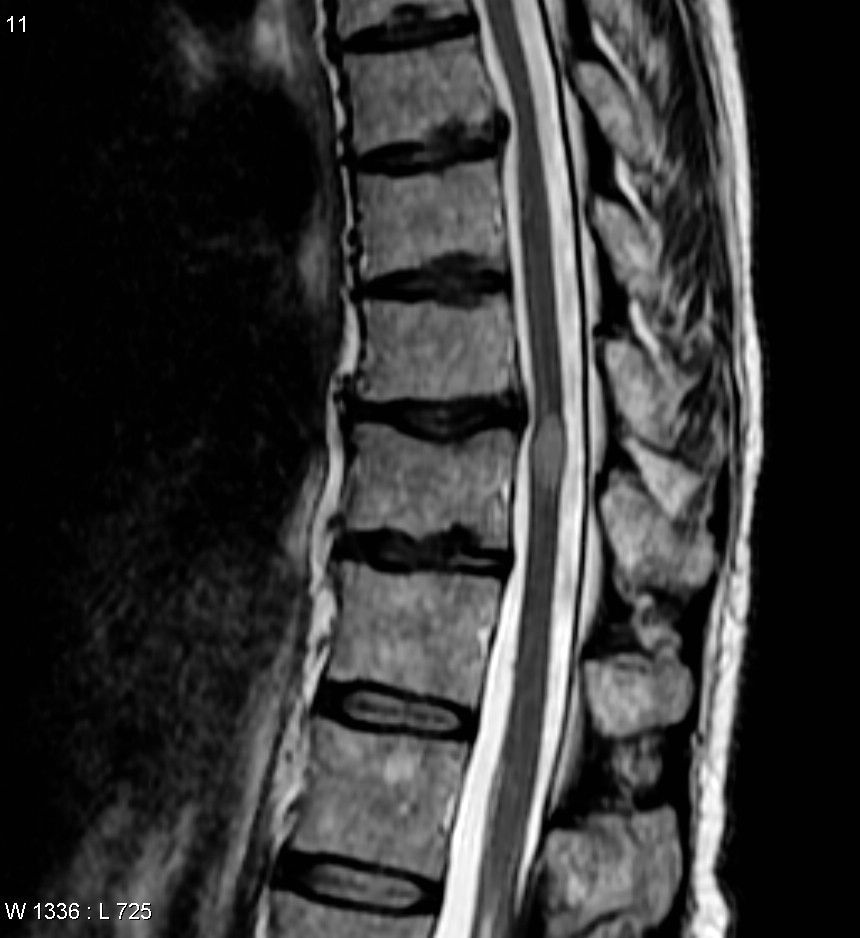

If your GP thinks you could have transverse myelitis, you should see a neurologist (a specialist in conditions of the nervous system) for a specialist assessment. Some of the tests you may need to confirm transverse myelitis are: neurological examination magnetic resonance imaging (MRI) scan lumbar puncture blood tests Sometimes your neurologist will do other tests to look for conditions that cause transverse myelitis. This might include CT scans.